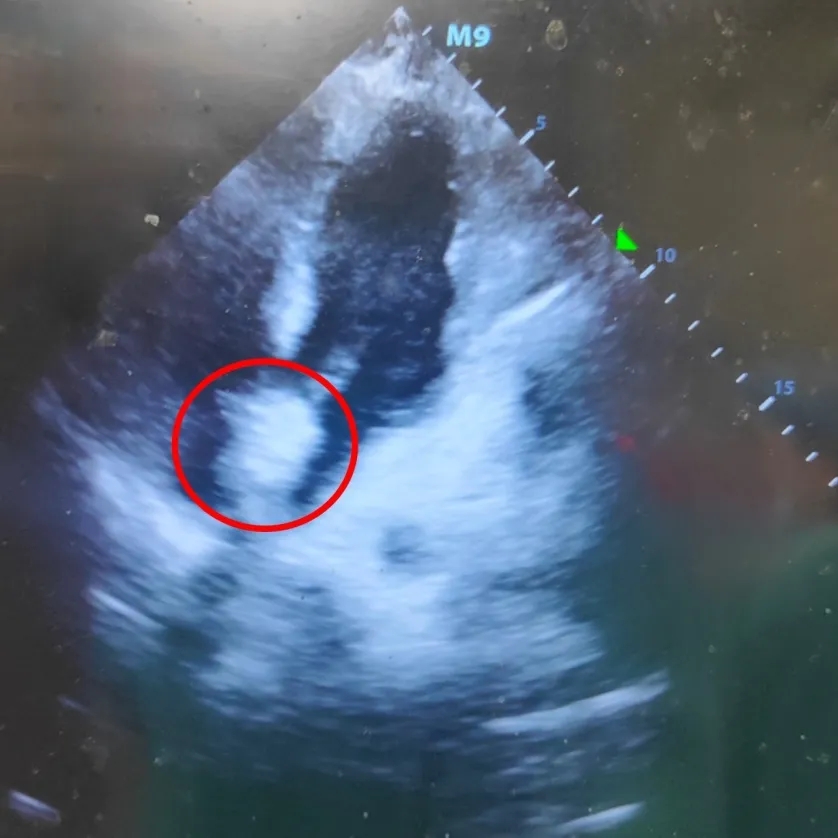

超声下可见封堵器盘面平整,位置固定,稳固夹持缺损

超声四腔心切面可见封堵器盘面贴合,形态良好

四腔心切面

双房心切面